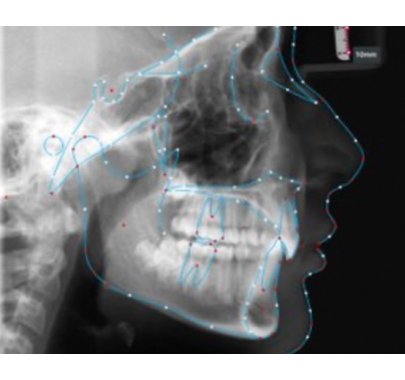

Grâce à nos algorithmes de tracé basé sur l’Intelligence Artificielle, nous assurons l’exactitude et la précision des tracés des repères dentaires sur les modèles numériques. Ces algorithmes permettent d’élaborer un plan de traitement et de poser un diagnostic de manière plus précise et efficace, nous permettant d’offrir de meilleurs résultats aux patients.